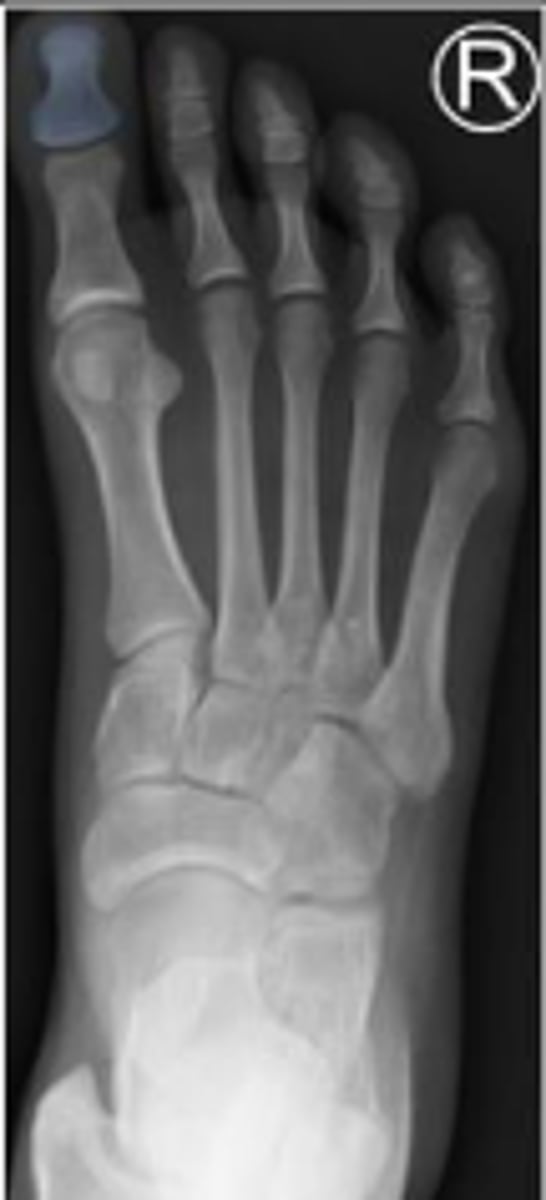

AP right foot

What is the name of the radiographic view?